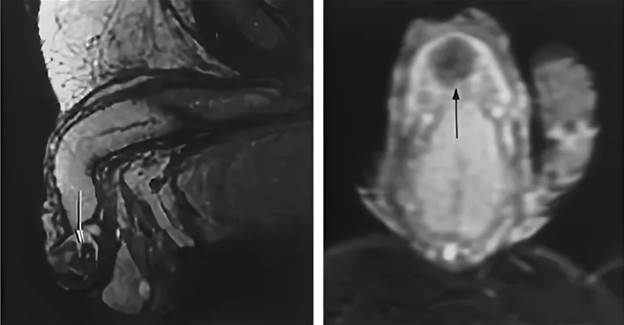

The penis is composed of 99% cavernous bodies and resembles a regular sponge. During an erection, it fills with blood and increases in size. The organ is supplied by two main blood vessels - the dorsal artery and the dorsal vein. Through the artery, blood enters the penis, and it is drained through the vein. Erection, in fact, is a manipulation of these vessels.

You see, when a man sees a beautiful girl, a signal is created in the brain to open special valves in the dorsal artery and close the same valves in the dorsal vein. After ejaculation (or when arousal subsides), the opposite happens - the valves in the artery close and open in the vein. Blood goes down from the penis, and it shrinks in size.

When the blood vessels weaken (observed in a huge number of men), there is a decrease in the tone of the vascular valves. The venous valves are particularly affected as they maintain blood pressure in the penis. They start to weaken. If the venous valves are "badly" fixed, the man experiences slow erection. If not fixed at all, impotence often occurs.